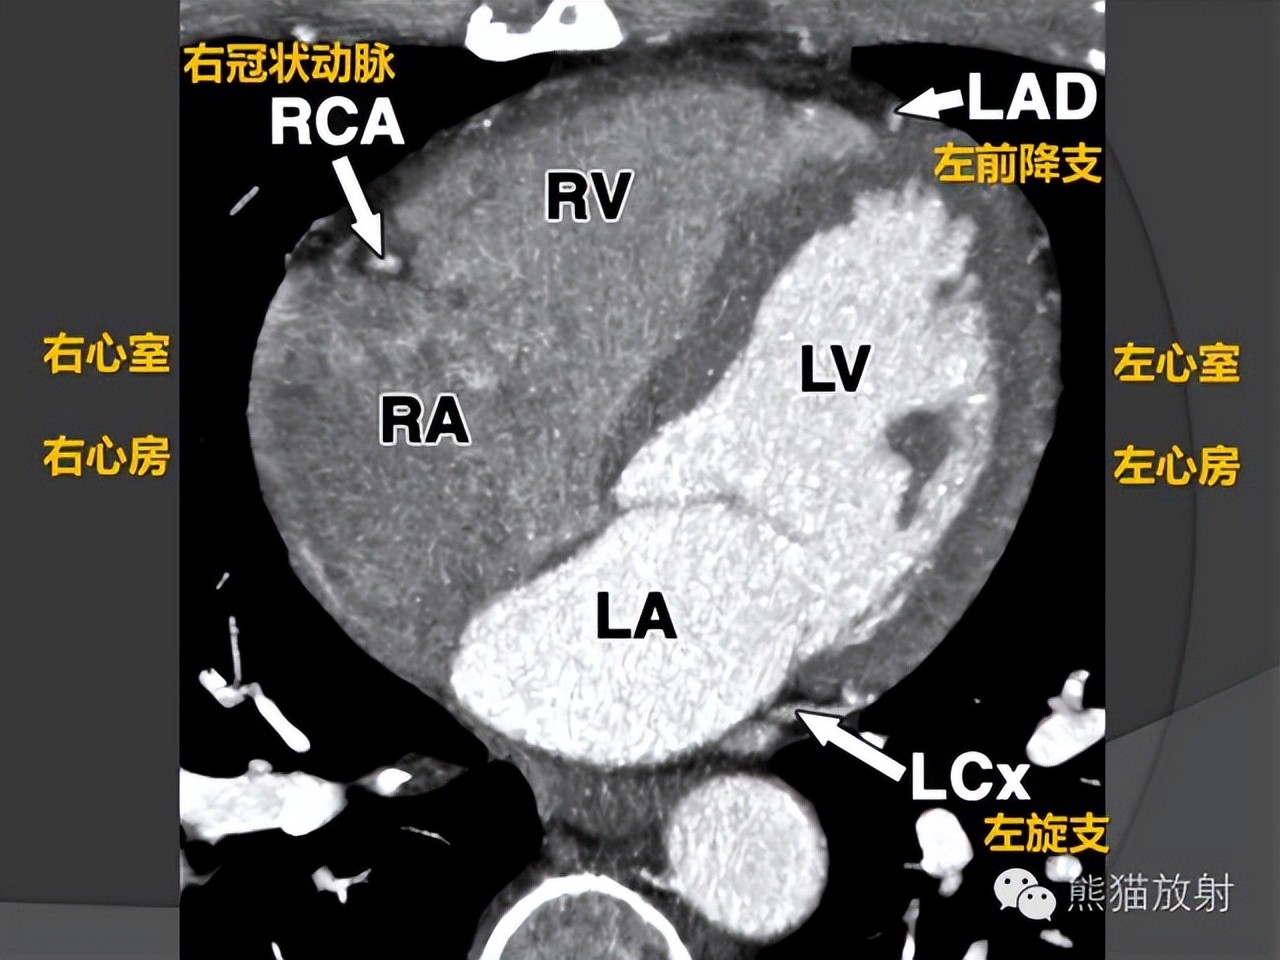

冠状动脉CTA解剖